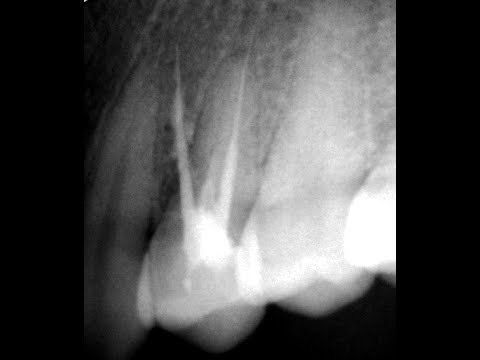

Как закрывать перфорацию на дне полости зуба, в области фуркации? Цемент МТА. Периодонтит. Часть 1.